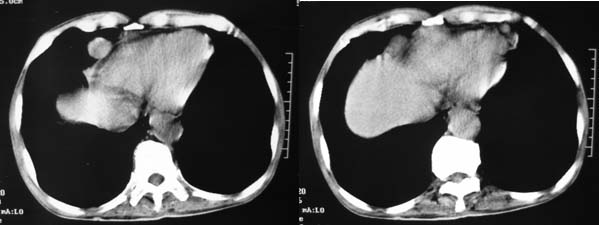

患者男性,74岁,腹部隐痛两月余,血、尿常规检查正常。大腿及腋下皮下各有两枚结节,最大者约3cm,活动度良好,b超提示为囊性。腹部ct平扫见,心包周围、肾周间隙多个大小不一软组织密度结节。

上腹部横断图象显示:心包,胃体小弯侧,肾等器官周围以及肠系膜腹膜后多发的大小不等的小结节样软组织密度影,部分境界不清,未见明显钙化.如此广泛的小结节样影,我认为首先考虑淋巴结肿大.能够引起淋巴结肿大的最常见的原因为:1.炎症(结核常见);2.转移;3.淋巴瘤.其中淋巴结结核不同程度可见钙化,而且这么大范围少见,暂不考虑.

右侧肾上腺区可见软组织密度肿块,密度欠均匀,未见钙化;右肾下极内侧可见实质局限性增厚并呈肿块样突出肾轮廓.

右侧心膈多角处还有一个类圆形结节哦